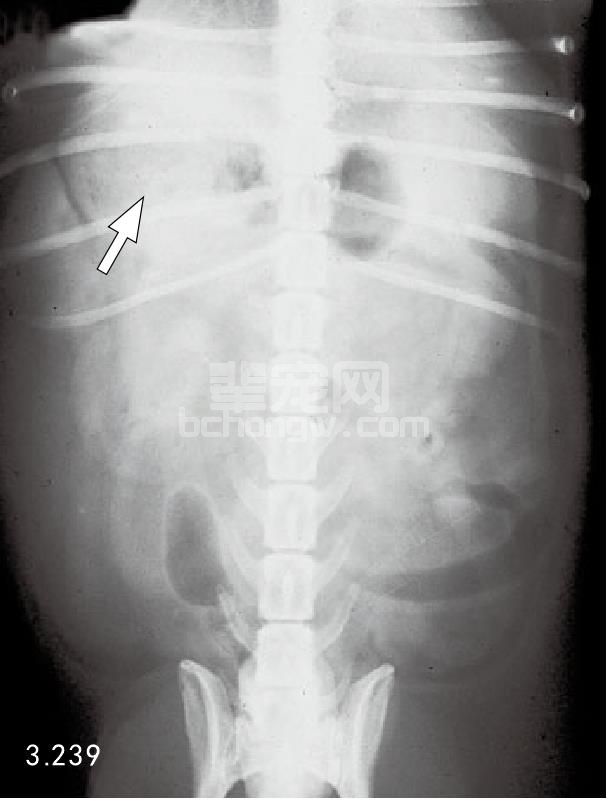

图3.239 图3.238的犬X线拍片检查是典型的急性胰腺炎,显现出右上腹部扇形液体密度增加(箭头所指),十二指肠向一侧移位。